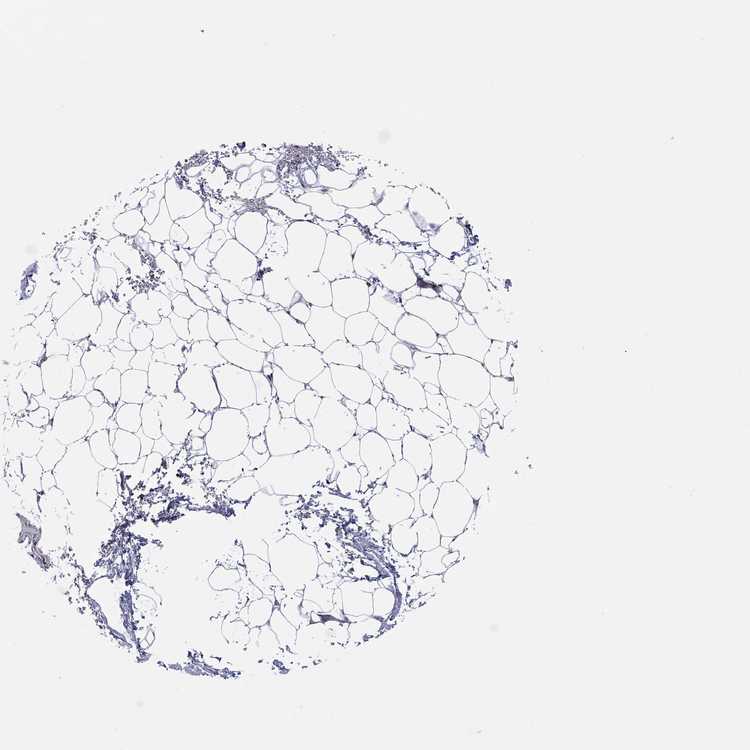

ADIPOSE TISSUE - Antibody stainingi

Antibody staining in the annotated cell types in the current human tissue is reported as not detected, low, medium, or high, based on conventional immunohistochemistry profiling in selected tissues. This score is based on the combination of the staining intensity and fraction of stained cells.

Each image is clickable and will lead to virtual microscopy that enables deeper exploration of all samples and also displays staining intensity scores, fraction scores and subcellular localization as well as patient and tissue information for each sample.

Antibody HPA001632Antibody HPA066527

Adipocytes HighNot detected